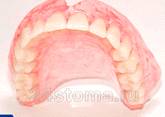

Полный съемный пластиночный протез состоит из базиса и искусственных зубов(рис.3). Базисом протеза служит пластинка из пластмассы. У протеза нижней челюсти базис располагается на альвеолярном отростке, а верхней челюсти - кроме того, еще и на нёбе. На базисе крепятся искусственные зубы, жевательная нагрузка от которых передается через базис на протезное ложе.

Рис.3 Полный съемный пластинчатый протез верхней и нижней челюсти.